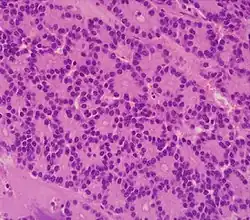

| Cancer type | Relative incidence[11] | Microscopy findings[11] | Micrograph | Immunohistochemistry markers[11] | Genetic alterations[11] |

|---|---|---|---|---|---|

| Pancreatic ductal adenocarcinoma (PDAC) | 90% | Glands and desmoplasia | ![]() |

||

| Pancreatic acinar cell carcinoma (ACC) | 1% to 2% | Granular appearance |

|

| Solid pseudopapillary tumor | Discohesive tumor nests surrounded by thin fibrous bands. | ![]() Low and high magnification[60] |

|||

| Adenosquamous carcinoma | 1% to 4%[61] | Combination of gland-like cells and squamous epithelial cells. | ![]() |

Positive for:

Negative for: |

| Pancreatic neuroendocrine tumor | 5% | Multiple nests of tumor cells | ![]() |